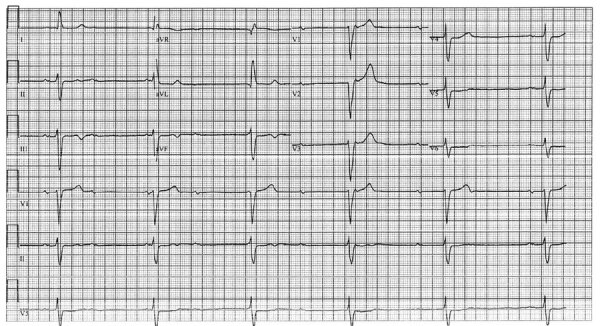

Description:Cardiac involvement in acute Q fever is rare. We report 2 cases of an advanced atrioventricular block in young adult patients in Israel who sought care for acute Q fever without evidence of myocarditis. Q fever should be suspected in unexplained conduction abnormalities, especially in febrile young patients residing in disease-endemic areas.